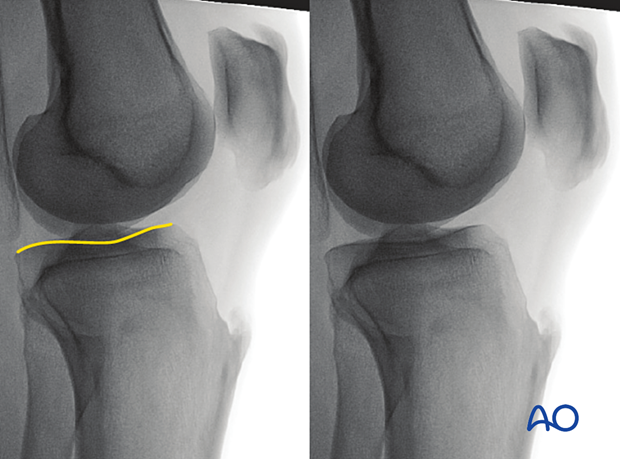

To obtain the optimal view for evaluating the lateral tibial plateau, start from the perfect lateral view and abduct the leg approximately 10-20°.

The optimal lateral view to assess the lateral tibial plateau is obtained when:

The following lines and landmarks can be observed:

This view is particularly useful to identify:

To obtain the optimal view for evaluating the medial tibial plateau, start from the perfect lateral view and adduct the leg approximately 10-20°.

The optimal lateral view to assess the medial tibial plateau is obtained when: